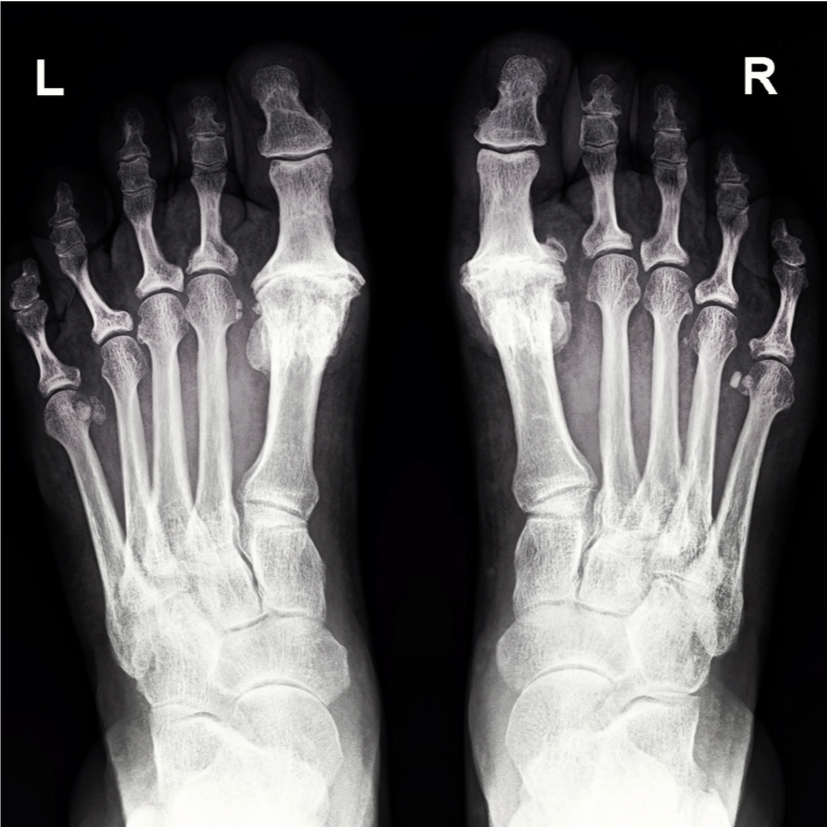

how is the diagnosis of hallux valgus made?

Clinical (probably best way, just looking at the foot)

Xrays: